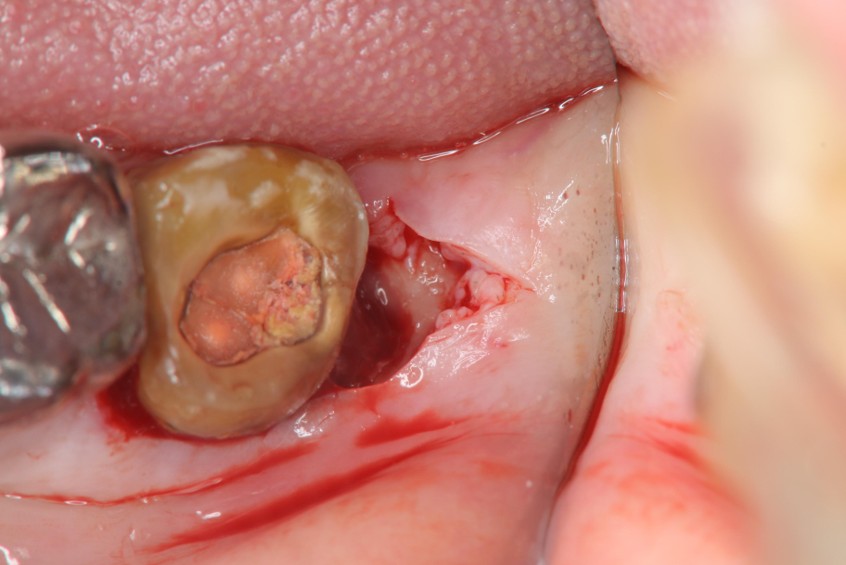

水雷射牙冠增長手術

6週牙齦癒合良好